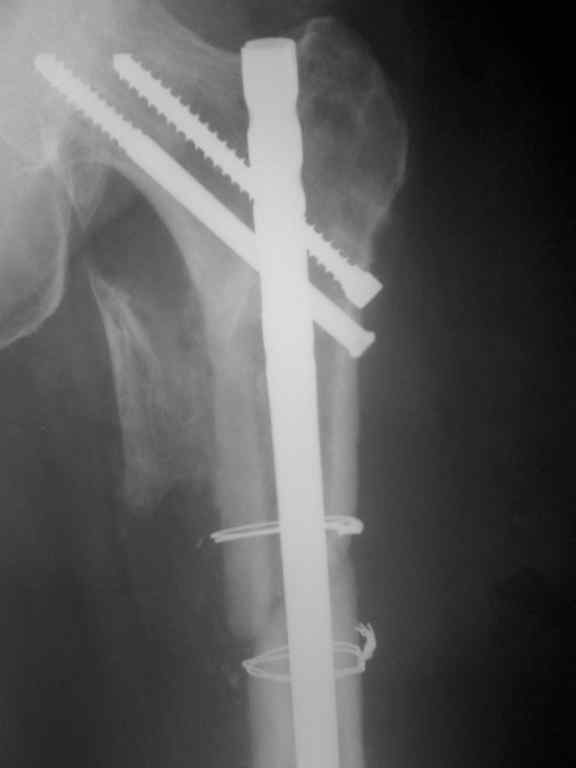

Р-гр после реостеосинтеза

Что ж, можно поздравить с успехом, форма бедра отлично восстановлена. Учитывая, что перелом подвертельный, вероятно, достаточно и этого реконструкционного стержня. Не очень понятно, зачем было открываться, и тем более использовать серкляж, но если все получится - победителя не судят.

К сожалению не открывая место перелома выполнить реостеосинтез не представилось возможным т.к канал проксимального отломка полностью закрыт костной тканью. серкляжом фиксирован крупный отломок не видный на Р-гр представляющий собой треть трубки задней поверхности бедренной кости.